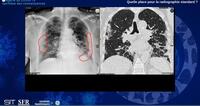

Radiologie et COVID

• toutes les informations utiles sur le portail de la SFR : http://www.sfrnet.org

et retrouver le webinair de la SIT